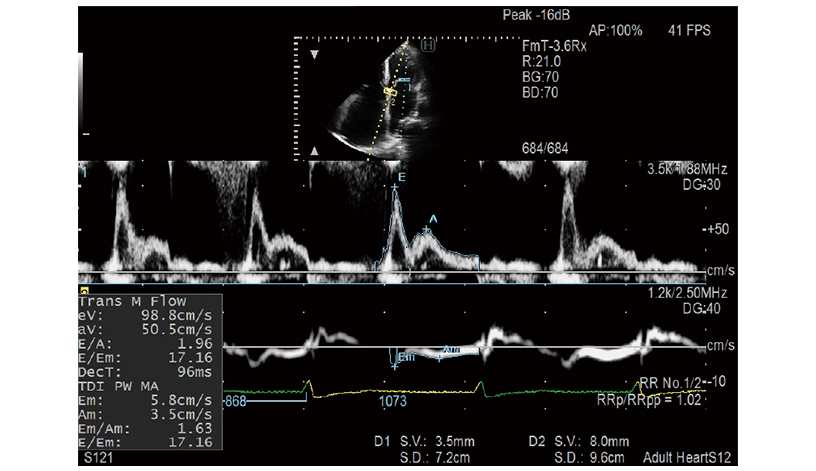

iDGD

Temel sol ventrikül (LV) diyastolik performans endekslerinden biri olan E/e’, Dual Gate Doppler kullanımında otomatik olarak ölçülür. Bu mod R-R Navigasyonu ile birlikte kullanıldığında, iDGD, otomatik olarak optimum kalp atışını algılayarak aritmi vakalar için etkili hale getirir.

- Dual Gate Doppler: Aynı kalp döngüsünde iki farklı konumdan Doppler dalga formunun gözlemlenmesini sağlar.

- R-R Navigasyonu: Stabil bir R-R aralığının otomatik olarak algılanmasını sağlar